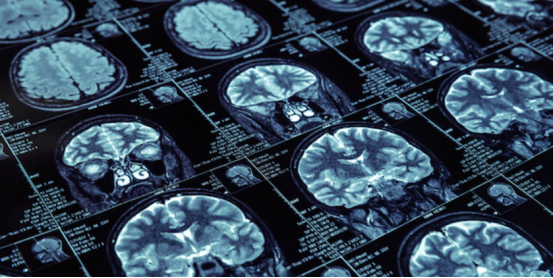

AI医学影像分析,则是利用机器学习、计算机视觉等技术,对医学影像数据进行自动化分析和诊断,并根据大量的定量特征,如形态、纹理、灰度、强度等,与基因、临床等其他数据进行关联分析,发现疾病的生物标志物和预后因素。

其AI产品InferOperate,通过对脑电图、脑功能成像等多种类型的神经影像数据进行深度学习,提取影像特征,定位病灶,从而为医生提供智能手术规划、术中全自动定位导航等。